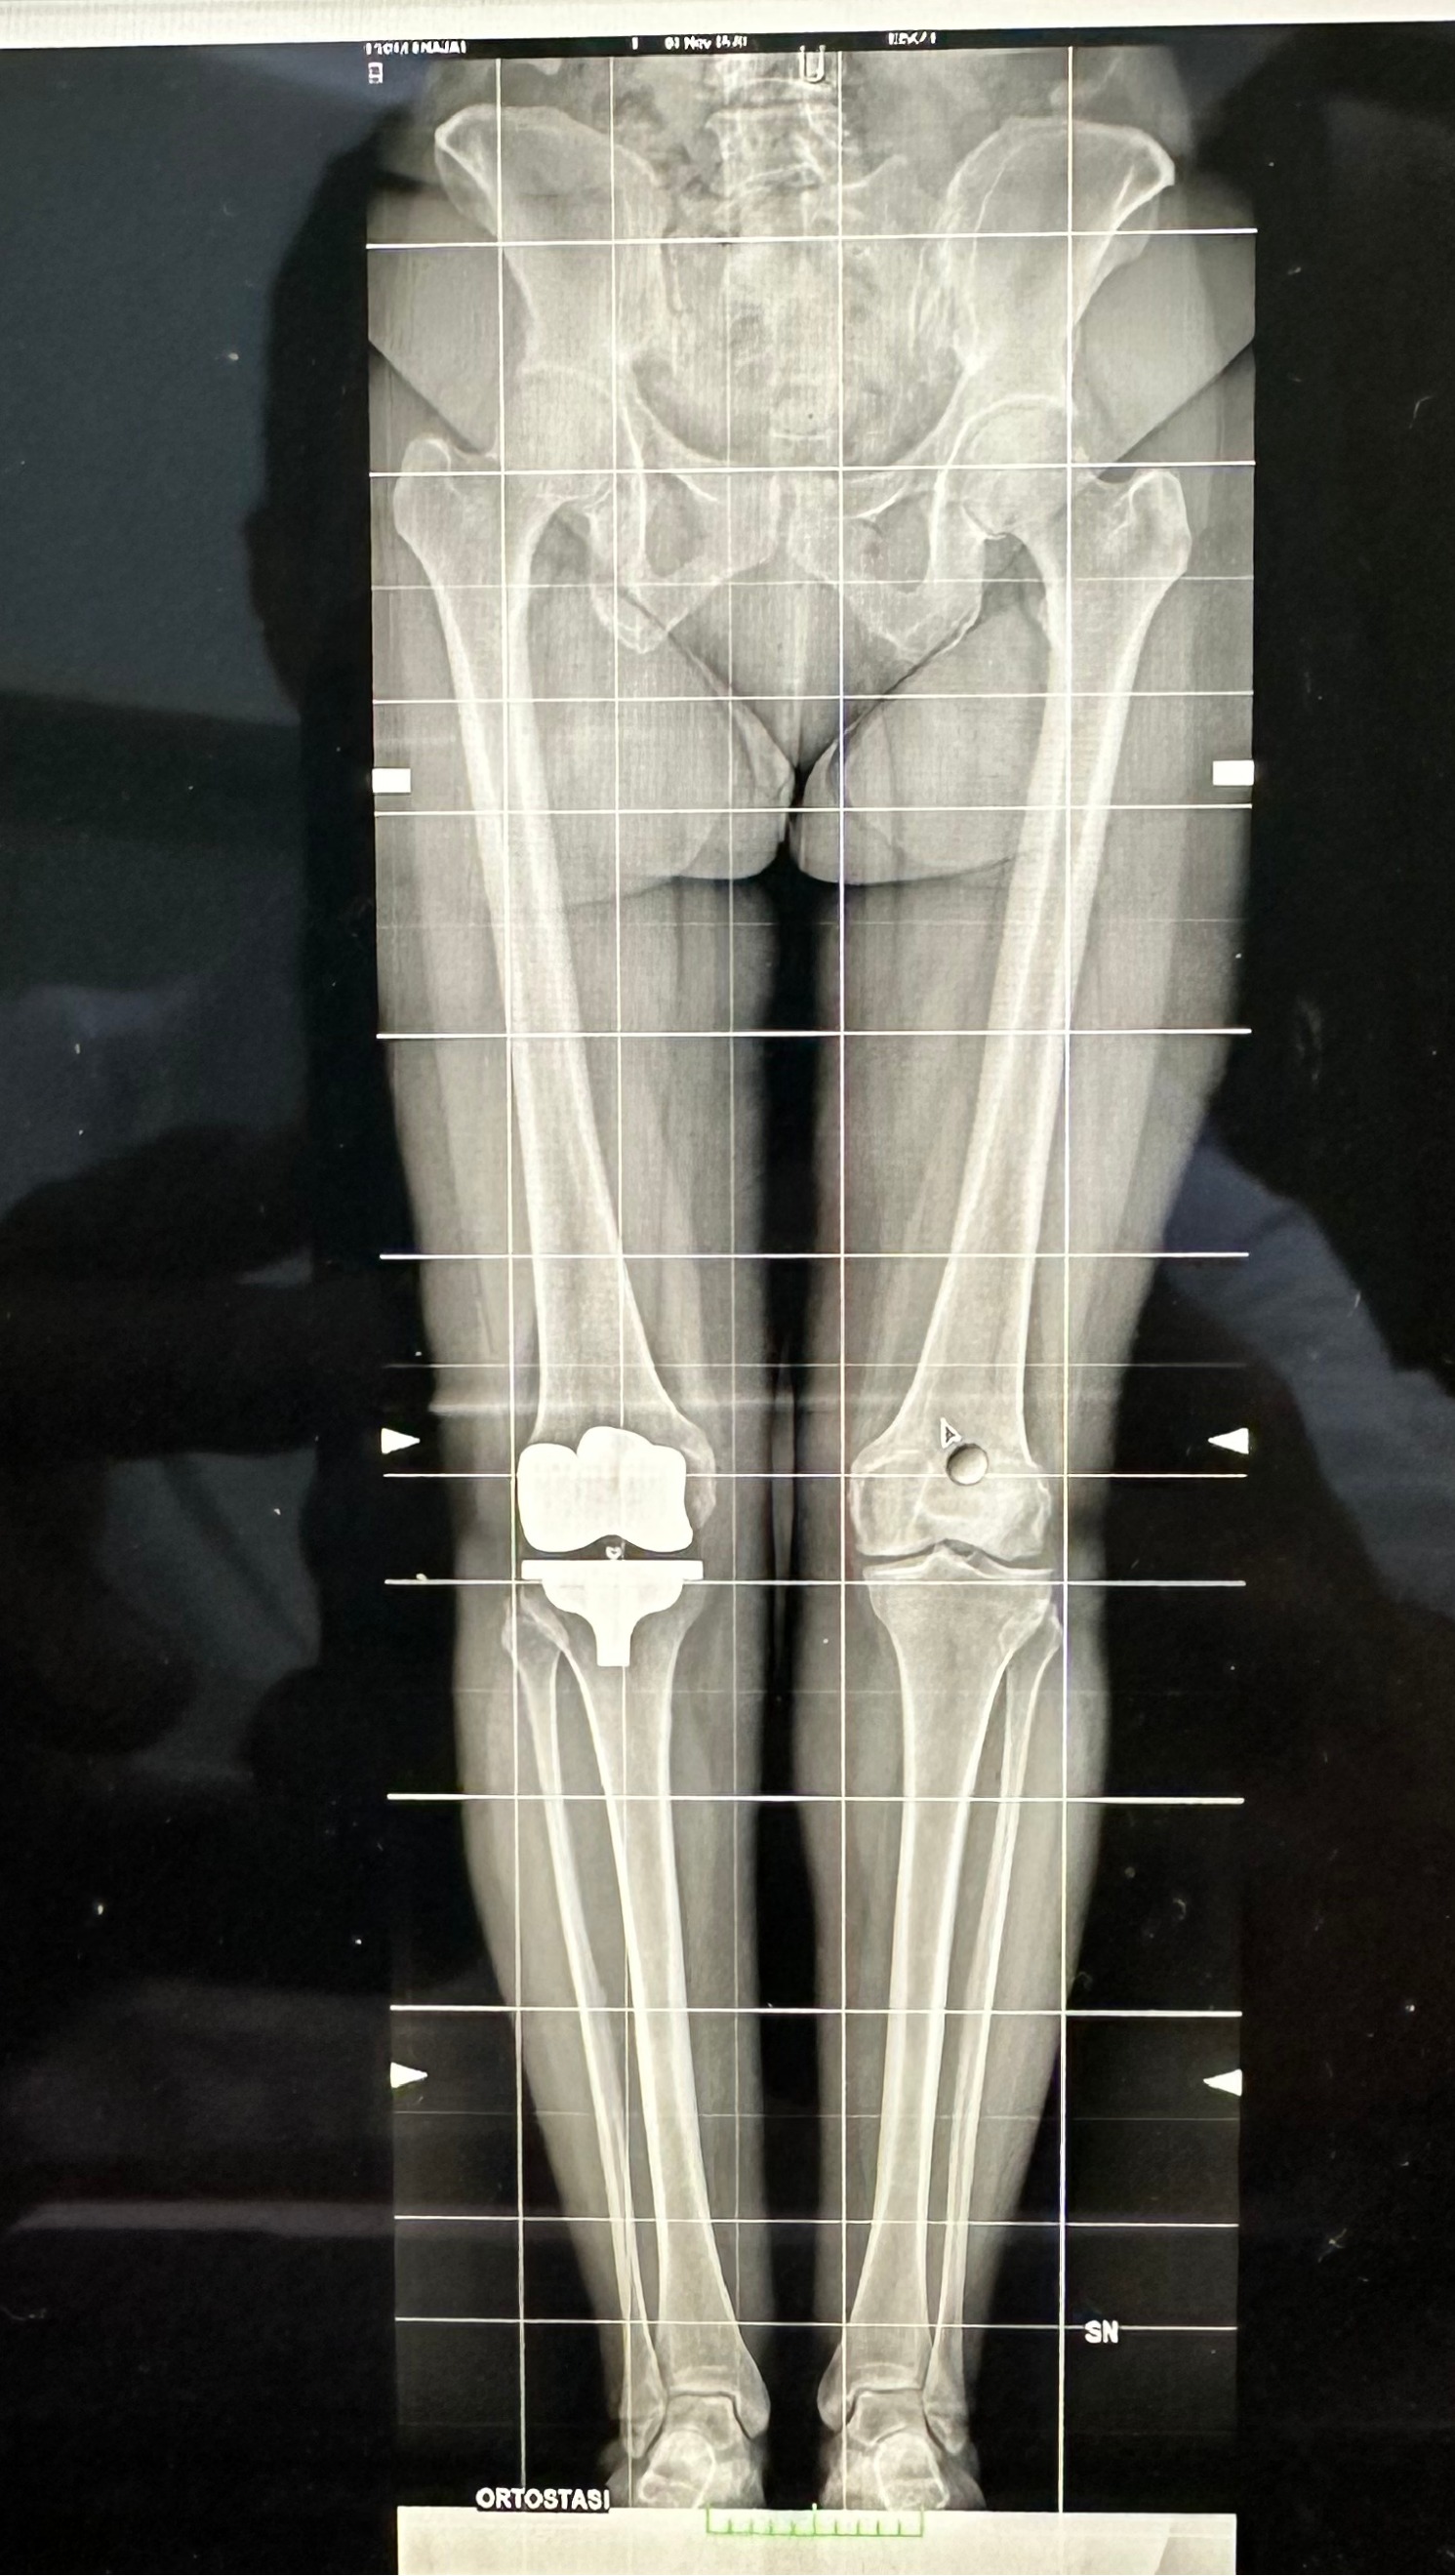

Radiografia Protesi Totale Ginocchio Allineamento Cinematico Radiografia Protesi Monocompartimentale